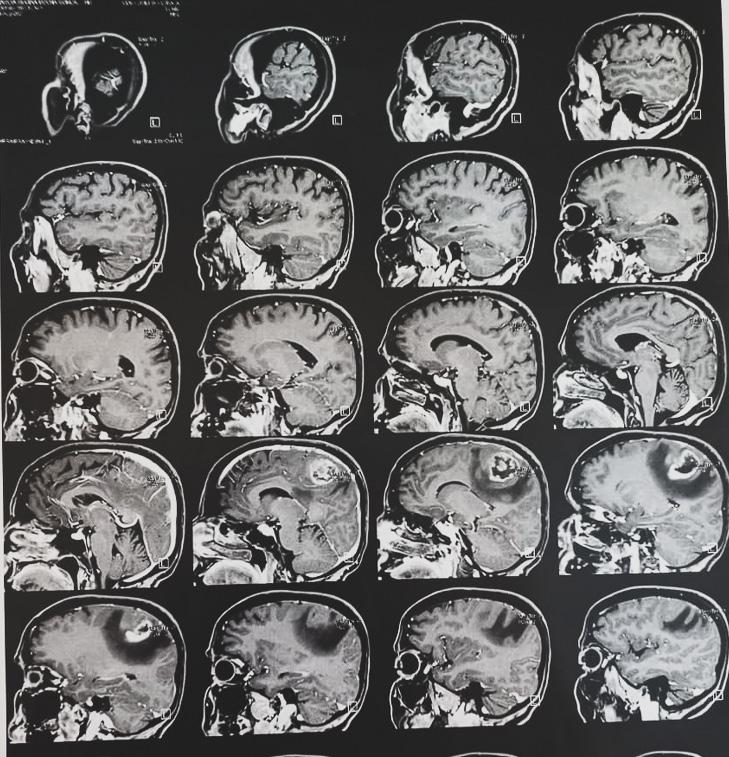

Câncer cerebral camuflado: diagnóstico e tratamento

O corpo humano funciona como uma fábrica, que precisa de todos os empregados para funcionar perfeitamente, possuindo um indivíduo em particular que administra tudo e dá as ordens, para que nada saia dos eixos. Pode-se afirmar que o cérebro é essa pessoa que comanda tudo, se ele falhar, consequentemente irá refletir em outra parte do corpo, como afetando a função motora. O câncer cerebral Glioblastoma Multiforme, começa a se manifestar dessa maneira, e ninguém sabe o que está acontecendo, porque é muito pouco discutido e abordado.

Glioblastoma multiforme faz parte do grupo dos gliomas, pois atinge um grupo específico, chamado de “células da glia”, elas auxiliam na composição do cérebro e nas funções dos neurônios, ou seja, ele irá se manifestar na falha de algum movimento motor, como dificuldade em andar, falar, entre outros. “Esse câncer apresenta quatro graus, igualmente aos outros, porém, na maior parte dos casos vindos até nós, estão no quarto grau, último e mais agressivo, por conta de se manifestar em uma região não ligada ao cérebro e muito menos aparentar ser um tumor, tornando o diagnóstico complicado de ser descoberto e revertido”, afirma a oncologista Priscila Braile, 38 anos, da Unimed de Limeira, São Paulo.

A rotina do ser humano consiste em acordar, fazer a primeira refeição do dia, escovar os dentes e sair para trabalhar. Pode não parecer, mas todas essas ações são comandadas pelo cérebro, ele manda e processa as ações para serem executadas. Quando um simples neurônio é atacado, vai se desprendendo dos outros, começa a deixar de exercer sua função, afetando toda a rotina do hospedeiro.

Márcia Regina Rocha Gonçalves, 55 anos, secretária de escola pública, esposa e mãe de duas meninas, viveu essa realidade. Pos-

suía uma vida normal, até que em uma tarde, andando de bicicleta, sentiu sua perna pesada e acabou caindo. “Jamais cogitaria que um joelho inchado, que dificultava o meu andar, era uma reação de um câncer cerebral agressivo, e sim algum problema ortopédico, me levando a quatro ortopedistas diferentes, me jogando para outros por não saberem o que estava acontecendo, me deixando perdida”, conta Márcia, que só conseguiu entender seu diagnóstico quando encontrou um oncologista.

Um Glioblastoma apresenta um quadro irreversível, muitas vezes com “prazo” de vida. Segundo o Registro Central de Tumores Cerebral dos Estados Unidos (CBTRUS) a taxa de sobrevida em 5 anos entre 20 a 44 anos é 22%; 45 a 54, 9% e 55 a 64, 6% de chance. “Por mais que não se tenha a cura e o tumor possua um crescimento mais rápido e ágil comparado a outros, o tratamento existe e prolonga o tempo de vida do paciente. Ele consiste em cirurgia para a retirada do tumor,

após sessões de radioterapia e quimioterapia. O paciente terá que ter um acompanhamento com neurologista, fisioterapeutas, terapeutas ocupacionais, fonoaudiólogos, nutricionistas e psicólogos”, informa a Dra. Priscila.

O câncer não afeta somente seu hospedeiro, mas também quem vive ao seu redor. As dores da pessoa se tornam as dos seus. Altair Aparecido Gonçalves, 56 anos, professor estadual de matemática e esposo de Márcia, comenta que procura passar o máximo de apoio e conforto nesse momento abalador para a família. “No primeiro momento, eu e minhas filhas sentimos muito, pergunta-se o porquê de tal doença, da gravidade, como ter sido evitada, enfim, uma notícia de um diagnóstico que abala e afeta a estrutura familiar. Portanto, em nosso particular, nos apegamos ainda mais a Deus, com muita fé e tomando de ensinamento para minhas filhas, o quanto a Márcia é uma guerreira, que luta dia após dia, não importando o resultado”, finaliza.